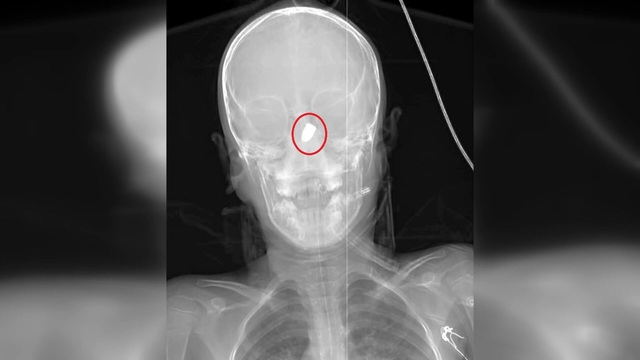

Şanlıurfa'nın Suruç ilçesinde 1 Haziran'da parkta bisiklet sürerken başına yorgun mermi isabet eden Sami Yusuf Kaya (6) ile 11 Haziran'da Antalya'nın Kepez ilçesinde evinin bahçesinde göğsüne yorgun mermi isabet eden Suriye uyruklu Abdurrahman Omar, hayatını kaybetti. Son olarak Adana'da 7 Haziran'da hobi bahçesinde karnına yorgun mermi isabet eden resim öğretmeni Burak Ateş (36) ile 9 Haziran'da sipariş hazırladığı sırada başına yorgun mermi isabet eden döner ustası Ramazan Malgir (39), yaralandı. ÇÜ Tıp Fakültesi Balcalı Hastanesi Acil Tıp Anabilim Dalı Başkanı Prof. Dr. Ahmet Sebe ve Adana Şehir Hastanesi Beyin ve Sinir Cerrahisi Bölümü'nden Doç. Dr. Ali İhsan Ökten, son dönemde çok sık gündeme gelen yorgun mermi vakalarıyla ilgili konuştu.

Prof. Dr. Ahmet Sebe özellikle yaz aylarında düğün mevsiminin de başlamasıyla birlikte bu vakaların hem çocuk hem yetişkin acilde sıklıkla görüldüğünü söyledi. Yılda yaklaşık 20-25 kişinin yorgun mermi kaynaklı acil servislerine başvurduğunu belirten Prof. Dr. Sebe, bu vakaların bazısının yapılan tetkiklerde tesadüfen tespit edilebildiğine dikkat çekti. Prof. Dr. Ahmet Sebe, "Bizim vatandaşlarımız silah sesi duyduğunda balkona, pencereye koşuyor. Bunun yerine gizlenmeyi, kendini korumaya çalışması gerekir. Silah sesi duyduğunuzda balkona, pencereye koşmayın; gizlenin. Çoğu zaman yorgun mermi fark edilmiyor, anlaşılmıyor. Tesadüf eseri bulduğumuz vakalar da oluyor. Kişi balkonda otururken bir bakıyorsunuz yere yığılmış. Sanki bir inme ya da beyin kanaması geçirmiş gibi görünüyor. Ancak hastaneye geldiğinde çekilen görüntülemelerde bunlar ortaya çıkıyor. Yorgun mermi kol ve bacak gibi uzuvlara geldiğinde hastaneye ulaşmalarında genellikle bir sıkıntı olmuyor ancak beyin, kalp ya da karın içindeki bir organa geldiğinde hastalar acile ulaşamadan hayatını kaybedebiliyor. İlk yardım uygulaması olarak bası yapılabilir ama iç organlara geldiyse kişinin yapacağı en doğru şey, 112 Acil Çağrı Merkezi'ne haber verip bir an önce hastayı sağlık kuruluşuna ulaştırmaktır. Buraya ulaştığında ise hastanın durumuna göre beyin cerrahi, göğüs cerrahi, genel cerrahi ya da girişimsel radyolojiye yönlendirerek, tedavisini gerçekleştiriyoruz" diye konuştu.

Doç. Dr. Ali İhsan Ökten de "Yorgun mermi, beynin sessiz bölgelerine geldiğinde çok fazla hasar yaratmayabilir. Ancak beynin derin bölgelerine doğru gittikçe orada damar yapıları da yoğun olduğu için beyin kanamalarına yol açıp ciddi sakatlanmalara, felç gibi durumlara ve hatta bazı vakalarda ölümcül sonuçlara neden olur. Bu vakalarda geçen yıllara oranla göreceli olarak bir artış olduğunu söyleyebilirim. Özellikle bireysel silahlanma oranının giderek artması, düğün, nişan, şenlik, festival, maç sonrasında veya asker uğurlamalarında bilinçsizce ateş açarak, sözde kutlama yapılması bu oranların artmasına sebep oluyor. Burada önemli olan tüm bunları denetlemek, kişisel silahlanmayı önlemek ya da cezaların artırılması yoluna gidilmesinin önleyici olacağını düşünüyorum" dedi.